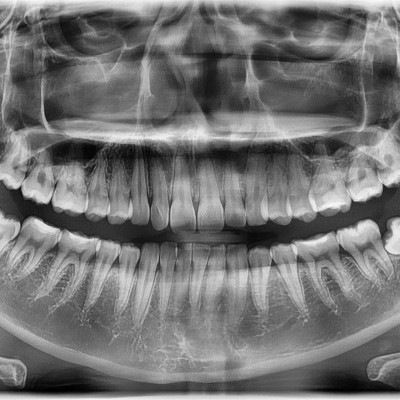

#28,38,48 사랑니 발치 N새글 #28,38,48 사랑니 발치 구강 외과 전문의가 당일 발치했습니다. -----------------------..